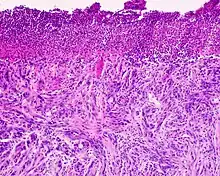

Desmoplastic melanoma, also known as neurotropic melanoma, or spindled melanoma[1] is a rare cutaneous condition characterized by a deeply infiltrating type of melanoma[2]: 696 with an abundance of fibrous matrix. It usually occurs in the head and neck region of older people with sun-damaged skin. Diagnosis can be difficult as it has a similar appearance to sclerosing melanocytic nevi as well as some nonmelanocytic skin lesions such as scars, fibromas, or cysts. Desmoplastic melanomas tend to recur locally, with distant metastasis being less common.[3]